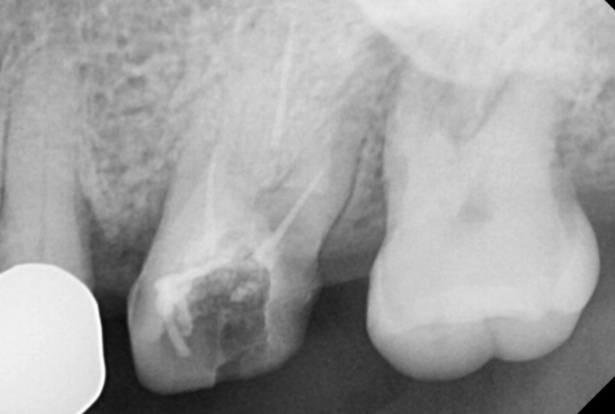

치아 크라운 빠짐 내부 모습입니다.

보철이 빠진 부분에 충치로 인해

치아가 깨지고

색깔이 노랗죠~?

한마디로 삭았습니다.

치아가 푸석푸석

기구가 닿기만 해도

부서져서 뽑고 강일역 임플란트 하기로 상담해드렸습니다.